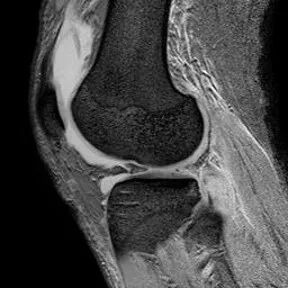

1、水平撕裂

2、较少见3、III级高信号与胫骨平台平行,到达半月板的游离缘或一侧关节面

(半月板水平撕裂)